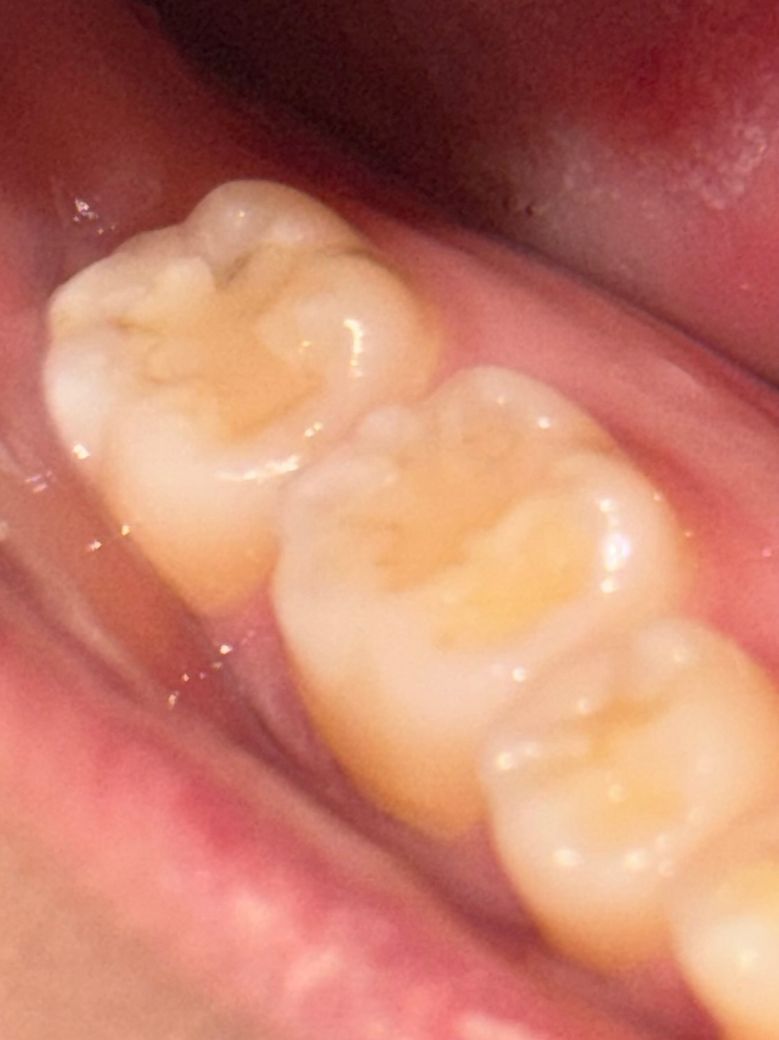

여기 충치가 생긴 게 맞는지 알고 싶습니다

최근에 치과에 갔는데 충치는 따로 없다고 해서 다행이다 하고 왔거든요 그런데 확인할 게 있어서 입 안을 보니까 맨 안쪽 어금니 레진? 채워진 부분에 회색으로 보이는 게 있어서 이게 충치가 맞을지 여쭤봅니다 사진으로는 조금 애매하게 보이는데 실제로 보면 그림자가 졌다기보다는 뭔가 있는 것처럼 보여서.... 엑스레이 찍었는데도 충치 없다고 하셨던 거라 더 잘 모르겠어서 치과 가보기 전에 여기에 먼저 올려봅니다

• 1번 째 사진

레진이 오래되다보면 치아와 레진 사이로 때가 낍니다 단순 변색이라고 보시면 될 것 같습니다

레진치료를 하고나서 시간이 지나면 틈세가 생기면서 착색이나 변색이 발생합니다. 착색이 된거니 크게 걱정은 안하셔도 됩니다.

사진으로 봤을 때 충치가 보이진 않습니다. 보철물 경계 부위가 떠 있거나 한다면 사진처럼 착색이 될 수도 있습니다. 크게 문제가 아닌 경우도 있을 수 있으니 자세한 확인을 위해서 치과에서 진료를 받아보세요